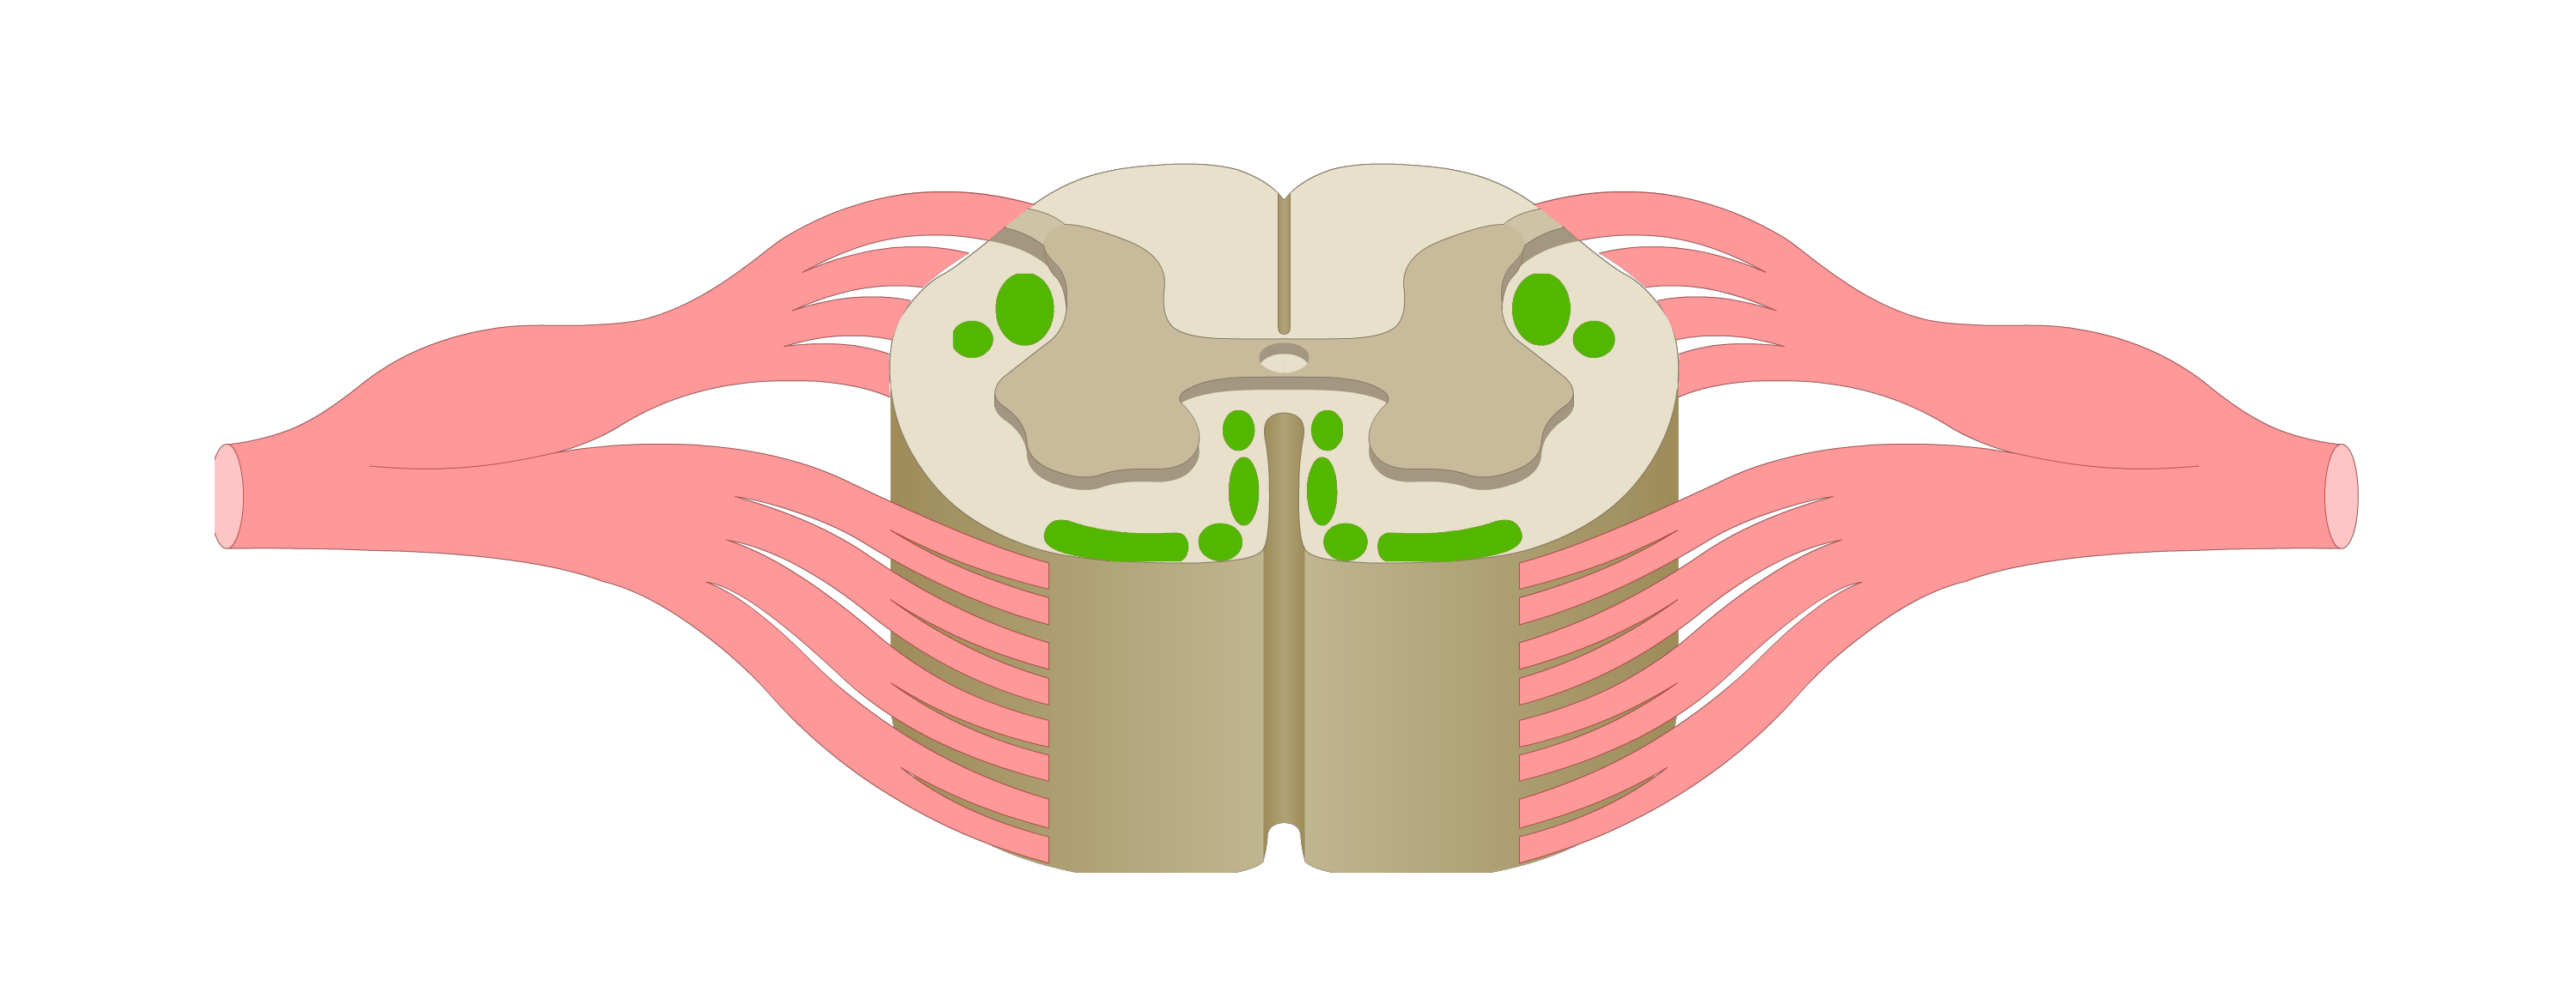

motor tracts

sensory tracts

dorsal root ganglion

dorsal horn

lateral horn

ventral horn

dorsal funiculus

lateral funiculus

ventral funiculus

central canal

ventral median fissure

dorsal median sulcus

afferent neuron

carries sensory action potential from receptor to CNS

efferent neuron

carries motor action potentials from integration center to effector organ

control/integration center

single/multiple synapses bw sensory & motor neurons; always in CNS